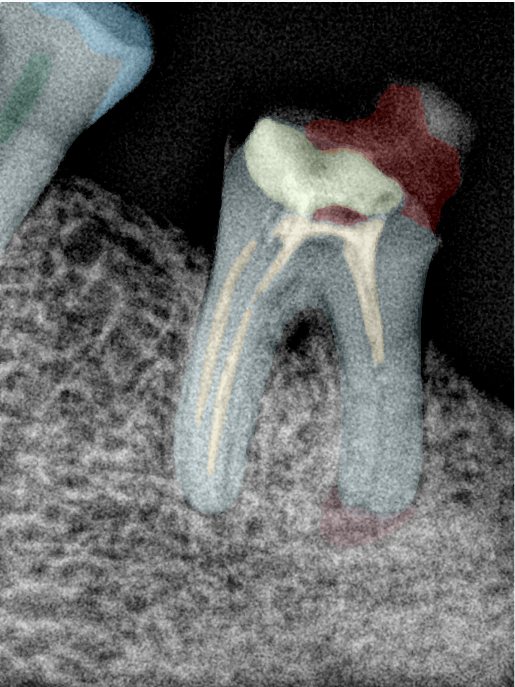

CR/DR 牙齿分割阶段记录

当前进展

- 完成了 CR/DR 牙齿相关分割训练

- 当前结果已经达到阶段预期,但仍有细节问题需要继续处理

相关测试

遇到的问题

- 训练过程中出现过 mask 下移问题

- 部分结果会出现 box 填充异常

- mask 边缘仍然有比较明显的锯齿感

参考

第二版算法问题测试

Updated: 2026-04-13(更新日期)

| 第一版 | 第二版 | 是否解决 | |

|---|---|---|---|

![]() | ![]() ![]() 边角识别有问题 龋齿识别不全 牙髓识别不全 | ![]() | 解决 |

![]() | ![]() 边角识别有问题 识别信息有误 自查(牙冠识别不全) | ![]() | 解决 |

![]() | ![]() ![]() 边角识别有误 大范围填充识别遗漏 | ![]() | 解决 |

![]() | ![]() 识别信息不全 | ![]() | 解决 |

![]() | ![]() ![]() 边角问题 牙胶识别不全 牙冠识别不全 | ![]() | 解决 |

![]() 换图片 | ![]() | ![]() 牙冠部分稍微白了一些就识别成小范围修补,部分判断异常 | 部分解决,修复类略敏感,牙冠部分稍微白了一些就识别成小范围修补,部分判断异常。 |

![]() | ![]() ![]() 牙冠识别不全 牙髓不全 根尖炎龋齿识别有误 | ![]() | 解决 |

![]() | ![]() | ![]() | 解决 |

![]() 换图片 | ![]() | ![]() | 解决 |

![]() | ![]() 牙冠识别有误 | ![]() | 解决 |

![]() 换图片 | ![]() ![]() 边角识别有误 | ![]() 修复类敏感 | 部分解决,图像过白,导致修复类判断异常。 |

![]() 换图片 | ![]() 牙冠识别不全 | ![]() 修复类敏感 | 部分解决,图像过白,导致修复类判断异常 |

结论:修复类出现了不鲁棒的情况,后续需要加入轮廓的扩充数据进行增强。